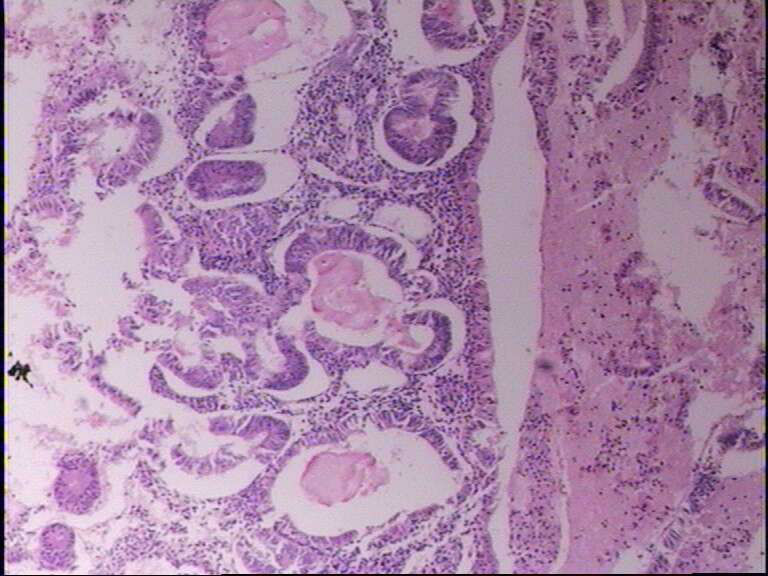

女43岁 不规则流血

• 宫内膜图1

图1

局灶复杂性增生伴轻度非典型增生

单纯性增生,局部间质崩解造成假拥挤。

单纯性增生。

子宫内膜单纯性增生,局灶区域呈复杂性增生

子宫内膜简单型增生过长

子宫内膜单纯性增生,局灶区域复杂性增生